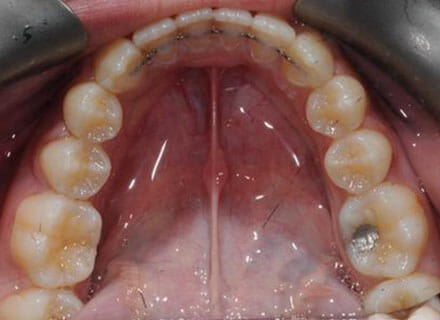

This patient came to us because she hated her smile: it was too narrow, the upper front teeth were all crowded into each other and twisted. She couldn’t eat a sandwich properly with the front teeth because of the gap – the open bite. We were able to expand both jaws to make space to align all the teeth without having to extract – in about 18 months using clear brackets.